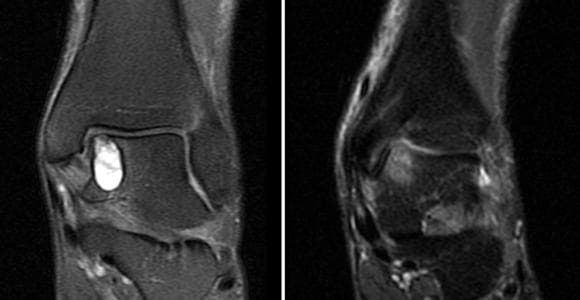

Ayak Bileği Lezyonu Talus Osteokondral

Ayak Bileği Lezyonu Talus Osteokondral Lezyonu, daha çok talusta nadiren de tibia eklem yüzeyinde meydana gelir. Bu lezyonların isimlendirilmesinde hala karmaşa yaşanmaktadır. İlk olarak 19. yy’ da fark edilen bu lezyonlar “osteokondritis dissekans” olarak adlandırılmıştır. Bu adlandırma günümüzde de kullanılmaktadır. Ancak son yıllarda gelişen tanı ve tedavi yöntemleri ile bu adlandırmada değişiklik olmuştur.

Ayak Bileği Lezyonu Talus Osteokondral oluşmasının sebebi çoğunlukla bir travmadır. Travma oranları, talusun medial ya da lateralinde olmasına bağlı olarak değişiklik göstermektedir. Lateral lezyonlarda travma oranı %98’dir. Medial lezyonlarda ise bu oran %70 civarındadır.

Talus kemiğinde görülen osteokondrol lezyonların bir kısmı, sporcu ayak bileği burkulmaları esnasında oluşmaktadır. Bir kısmı da mikro travmalar, basma bozukluklarının ve dengesiz yüklenmelerin sonucu oluşmaktadır.